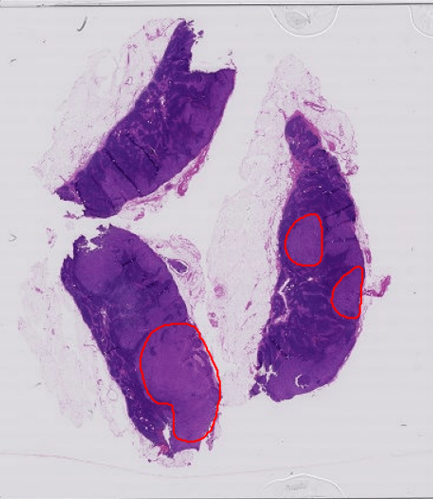

Inverse Problems in Digital Pathology